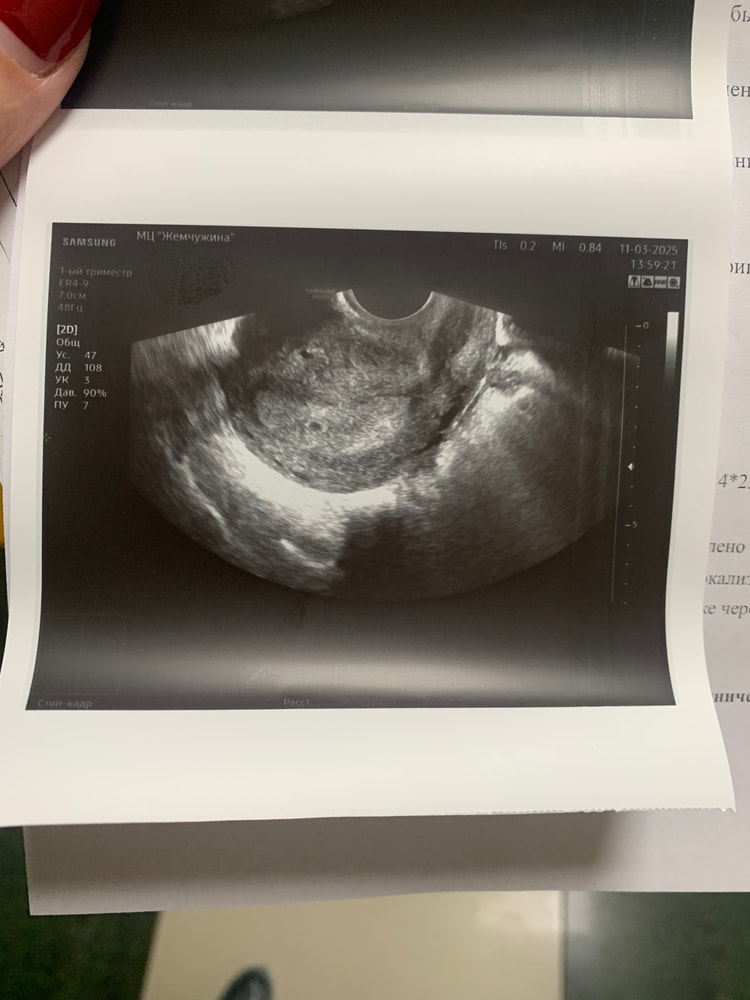

Я делала рано узи. У меня в день типа месячных вечером на бумаге после похода в туалет была светло-коричневая мазня. На след день я поехала в больницу, потому что распереживалась. Узи сделала трансвагинально, был срок тогда 4+1 недели, увидели только жт и что-то крохотное еще. Выделений больше не было, хгч в динамике показал рост. Через 3 дня я узи повторила тоже трансвагинально, увидели маленькое плодное яйцо. Тогда хгч был 2100.